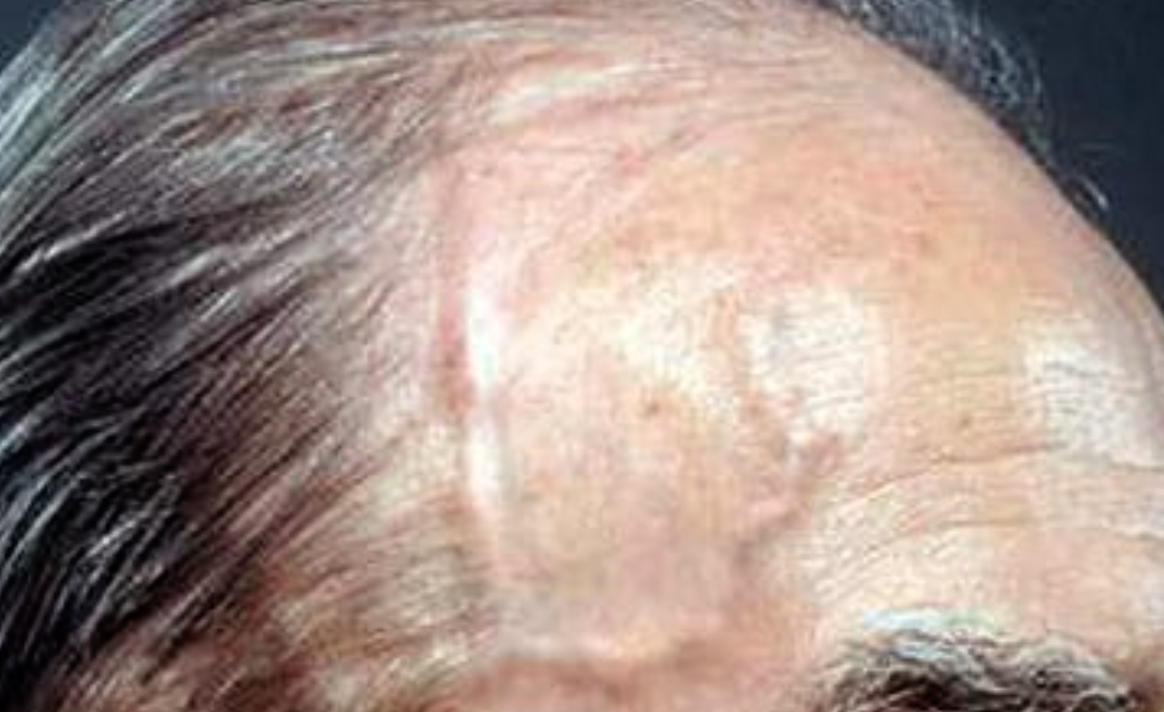

Case 1 Z

A 70 years old male presented with a new onset headache and loss of

vision for 72 hrs. He also complained of jaw claudication on chewing and

talking.

Mention 3 expected features of the temporal artery which may be present in this condition?

- Weak or absent pulse,

- artery tenderness or enlarged and

- beaded appearance of the artery

Mention 1 blood test which you will do during diagnostic work up?

- ESR

- CRP

Which imaging technique can be helpful in diagnosis?

- Doppler US

What will you do for a definitive diagnosis?

- Temporal artery biopsy

Mention 2 neurological complications of this condition?

- Anterior ischemic optic neuropathy (blindness) - acute vision loss

- Diplopia (due to 3rd, 4th, or 6th nerve palsy)

- New onset Headache

- Jaw claudication

What is the treatment of this condition?

- Corticosteroid